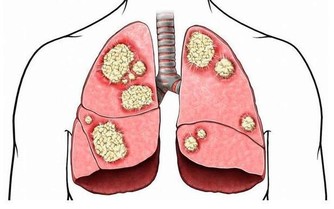

5. 心腦血管病

由於打呼嚕憋氣時人體缺氧,會引起冠狀動脈內皮損傷,脂質在血管內膜沈積,紅細胞增多,血液黏度隨之增加,最終引發各類心腦血管疾病,如:血栓、中風、心絞痛、心肌梗死等,且患者在睡眠中突發心肌梗死和腦梗塞的幾率是正常人群的3倍!

另外,在治療心血管疾病時,不要忽視打呼嚕憋氣對心血管病的危害。